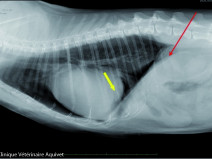

• Mise à jour des connaissances en imagerie médicale

La radiographie reste l’examen de première intention pour évaluer le thorax. Cet examen est facile à réaliser, peu couteux, et apporte de nombreuses informations si les bases anatomiques, sémiologiques et d’interprétation sont connues.

L’AFVAC section Antilles-Guyane vous propose dans ce sens une formation sur la radiographie du thorax.  Cette formation aura pour but de reprendre des él...